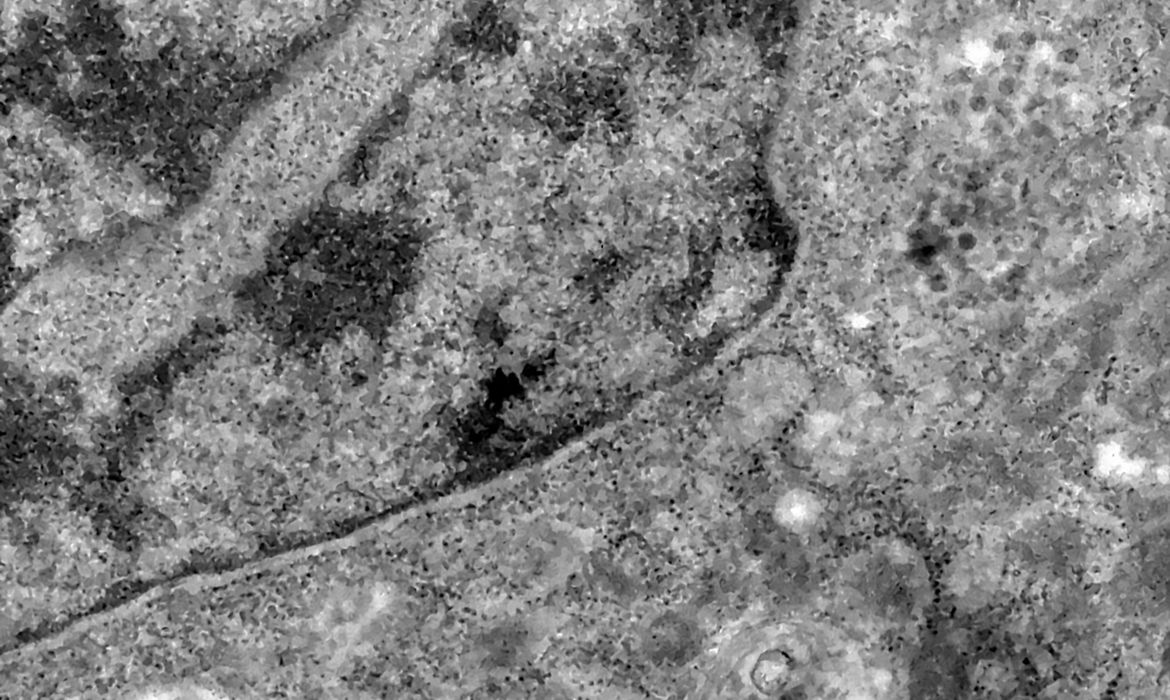

Nos casos analisados, constatou-se que a variante é portadora de dezenas de mutações genéticas que podem afetar os índices de contágio e de letalidade. A OMS, entretanto, afirmou que ainda não há estudos suficientes para afirmar as propriedades da Ômicron, mas que já existem esforços científicos acelerados para estudar as amostras. Um time de cientistas de universidades da África do Sul está decodificando o genoma da Ômicron, juntamente com dezenas de outras variantes do novo coronavírus.

Tulio de Oliveira, diretor do Centro para Respostas e Inovações Epidêmicas da universidade de KwaZulu-Natal, afirmou em coletiva de imprensa que a variante Ômicron possui “uma constelação incomum de mutações”. A variante Delta, por exemplo, possuía duas mutações em relação à cepa original do novo coronavírus, enquanto a Ômicron possui cerca de 50 – 30 delas localizadas na proteína Spike, responsável por infectar células saudáveis, explicou o brasileiro.

Foto: Débora Barreto/ Fiocruz